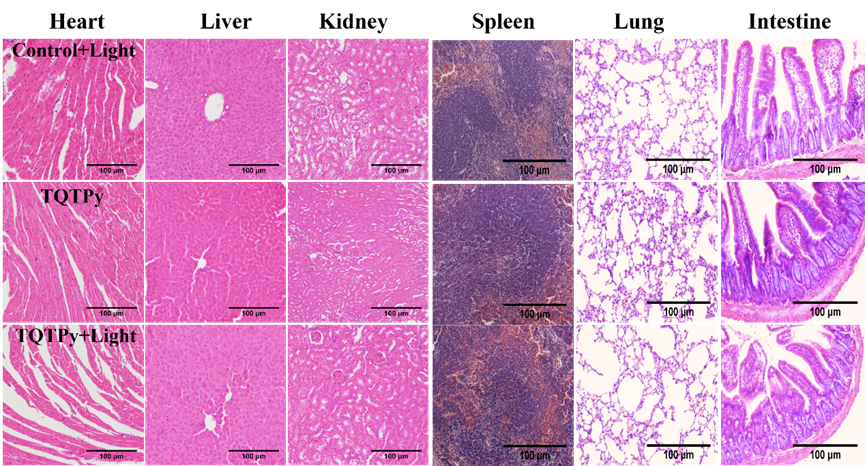

此外,通过H&E染色法,作者进一步评估了TQTPy的生物相容性。如图10所示,三组小鼠的心脏、肝脏、肾脏、脾脏、肺部和肠道等重要器官的组织切片均未观察到明显的组织损伤或炎症迹象,这有力地证明了TQTPy对于体内的主要器官具有较低的毒性。

图10. 不同组小鼠组织切片(心、肝、肾、脾、肺、肠)的 H&E 染色图像